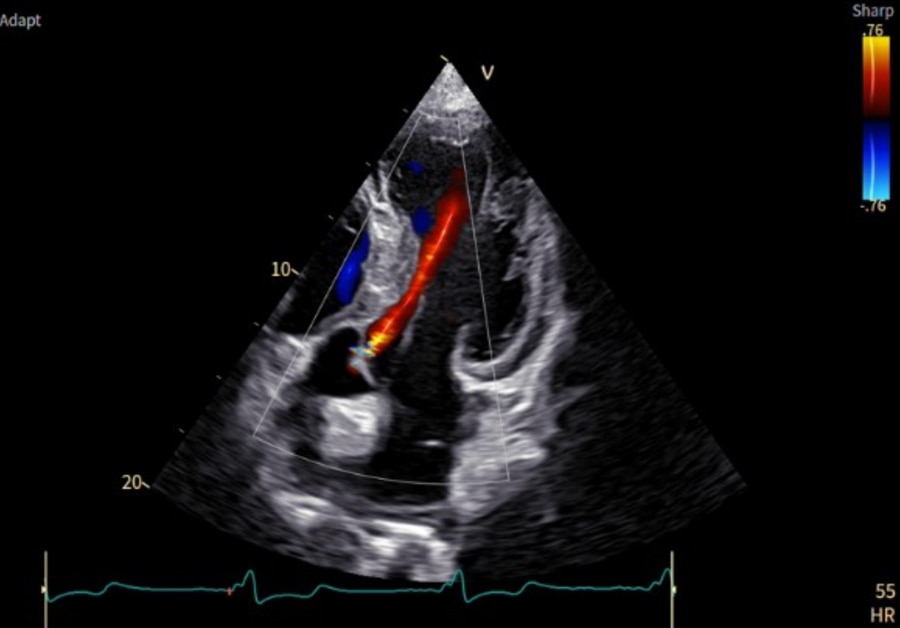

「Vivid Pioneer」は、これまで検査者が手作業で行っていた血流解析をAIが自動で行い、短時間で安定した測定プロセスを提供します。また、心臓の主要な部位(左心室と左心房)の動きや形を三次元で自動分析し、検査者間の標準化を支援します。そのほか、次世代の画像エンジン機能により、細部の見やすさ(空間分解能)や色の見やすさ(カラー感度)が向上し、より高精度な心臓の立体画像を描出します。

AIが血流を自動解析